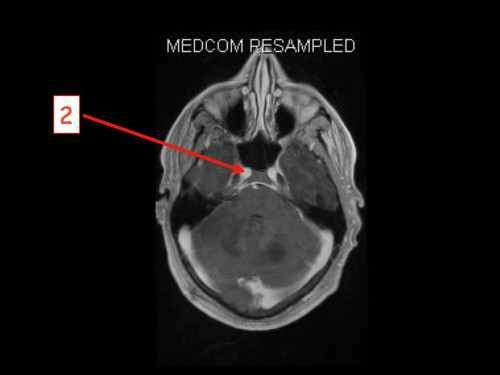

3. Schwindel und Kopfschmerzen, 3 Jahre nach Phäochromozytom-Resektion

Schwindel und Kopfschmerzen, 3 Jahre nach Phäochromozytom-Resektion

19-jähriger Mann. Er klagt seit mehreren Wochen über Schwindel und Kopfschmerzen. Im Alter von 16 Jahren sind er und sein Zwillingsbruder an einem Phäochromozytom operiert worden.